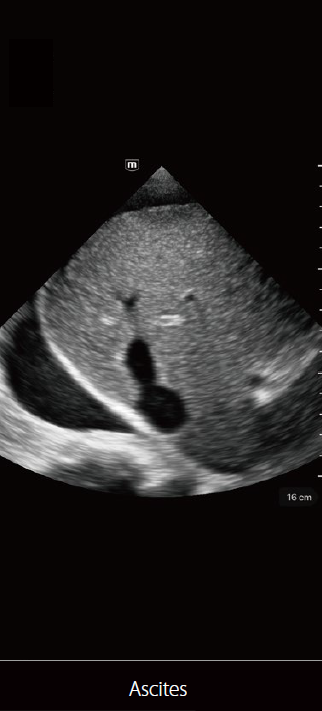

TE Air

صور متعلقة